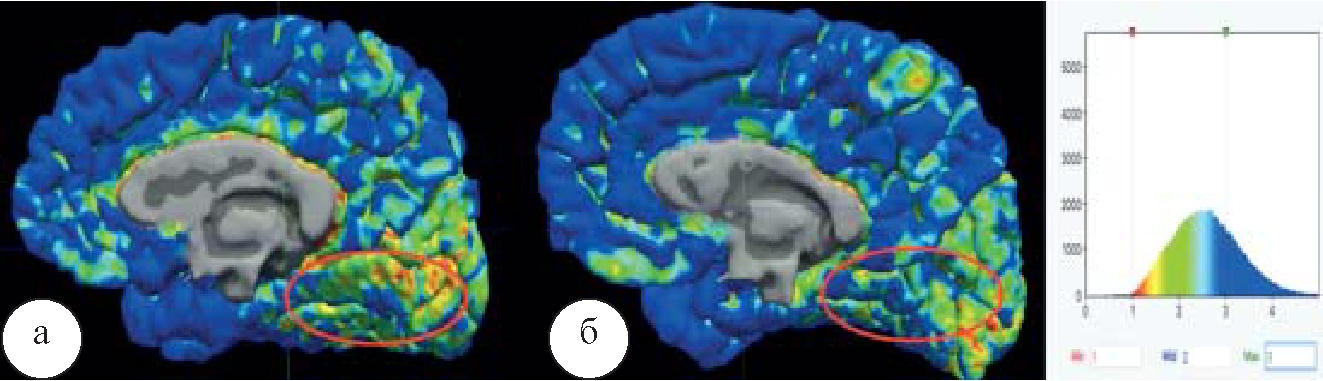

Более всего в СПРР головного мозга была снижена функциональная ценность ПКл, а целый ряд структур, таких как МПФК, левая миндалина и передняя часть поясной извилины, вообще выпадали из этих взаимодействий. Факт такого снижения пока остается не до конца понятным. При этом целый ряд структур наоборот, увеличивает свою активность по сравнению с нормой и наркоманией (рис. 2), а также, по данным анализа графов, начинает обладать большей, нежели чем в норме, функциональной ценностью. К таким структурам в первую очередь могут быть отнесены правый бледный шар, левая скорлупа, гиппокамп, левое прилежащее ядро. Наиболее страдающими структурами, по сравнению с нормой, в этой конфигурации сети являются хвостатые ядра, миндалины. Значительно снижается функциональная ценность элементов ПКл в СПРР. На рисунке 2 размер сфер, обозначающих хабы нейросети, соответствует значениям их функциональной ценности; при патологии значительно страдает и прекращает достоверно определяться функциональная активность МПФК, выполняющей функцию контроля.

Рис. 2. Функциональная ценность подкорковых и контролирующих структур по результатам анализа на основе теории графов: а – при синдроме зависимости от алкоголя; б – в норме, p<0,05

При оценке коннектометрических показателей головного мозга при синдроме зависимости от алкоголя отмечается полное разобщение СПРР и подкорковых структур, а также обеднение связности в лимбической системе, выпадение элементов СПРР (рис. 3).

Рис. 3. Функциональные коннектомы: а – при синдроме зависимости от алкоголя; б – в норме, p<0,05